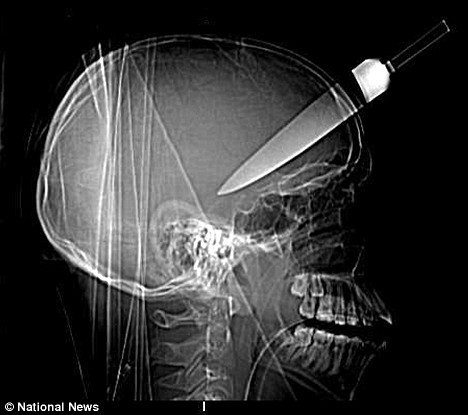

October 1, 2008: Knife in the head

This harrowing picture shows an X-ray of a 15-year-old boy's skull after a five inch knife was plunged into his head.

Amazingly the teenager survived the stabbing and ten months on from the attack has enrolled in college.

The boy and two other youngsters were attacked when they tried to stop a friend being robbed at a bus stop in Walworth, south London.

The muggers responded by using a kitchen knife to stab one of the boys in the forehead, another twice in the back and a third in the shoulder.

He survived because he was rushed to hospital with the knife still sticking out of his head and doctors managed to operate in time.

X-rays released by police show how deep the knife penetrated, while still missing the boy's brain. Surgeons said if anyone had tried to take it out he would have died.

The boy's two friends also recovered after the attack outside Tesco in the Old Kent Road on 28 November.